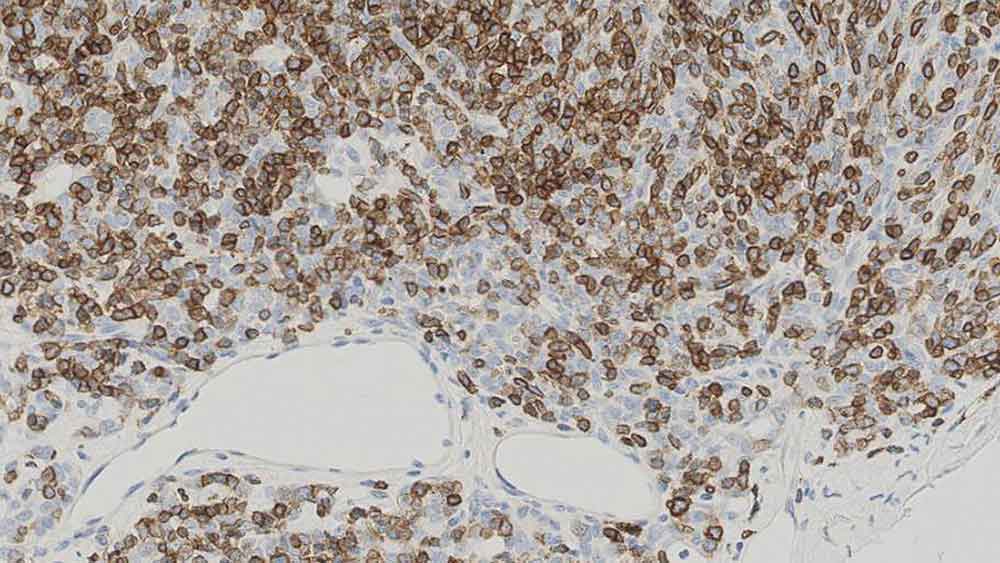

Human thymoma: immunohistochemical staining for CD1a. Note the neoplastic cells show a moderate to strong and distinct membrane staining reaction. CD1a: clone MTB1

Clone MTB1抗体は、胸腺皮質細胞、表皮のランゲルハンス細胞、真皮および扁桃重層扁平上皮の指状突起細胞を検出します。Clone MTB1抗体は、扁桃胚中心の周囲にある一部のリンパ球も検出することがあるため、CD1b抗原との交差反応性が示唆されます。